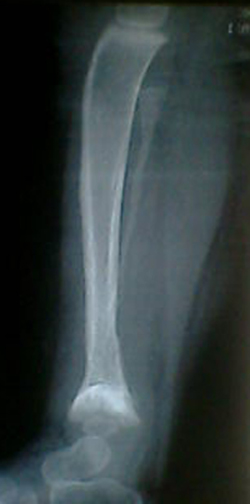

腓骨骨质溶解,大块骨质溶解症可能性大,建议进一步询问病史,进一步检查。有既往片价值更高。

考虑骨肉瘤

考虑尤文肉瘤可能

左腓骨呈容骨性破坏。骨皮质及骨髓腔均破坏,下段骨不连续,周围软组织肿胀。考虑骨尤文氏肉瘤可能性大。

尤文肉瘤的明显软组织肿块与较小骨质破坏不成比例,本例似乎不符合。应考虑腓骨骨质溶解,建议询问家族史。